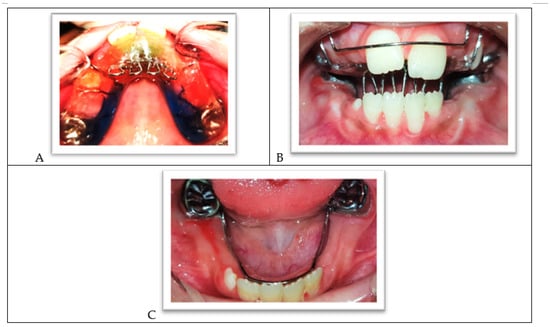

- A pinpoint pulp exposure happened (Figure 6A).

- A coronal pulpotomy was completed by removal of coronal pulp tissue.

- Hemostasis was achieved using 5% sodium hypochlorite and MTA placed as a dressing material over pulp orifices (Figure 6B).

- The tooth was restored like teeth #36 and #46.